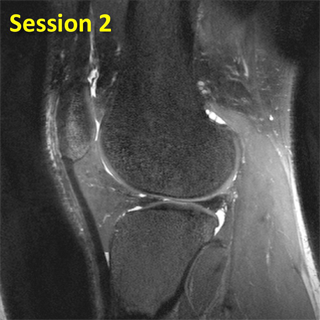

Initial visit

Image from the first session.